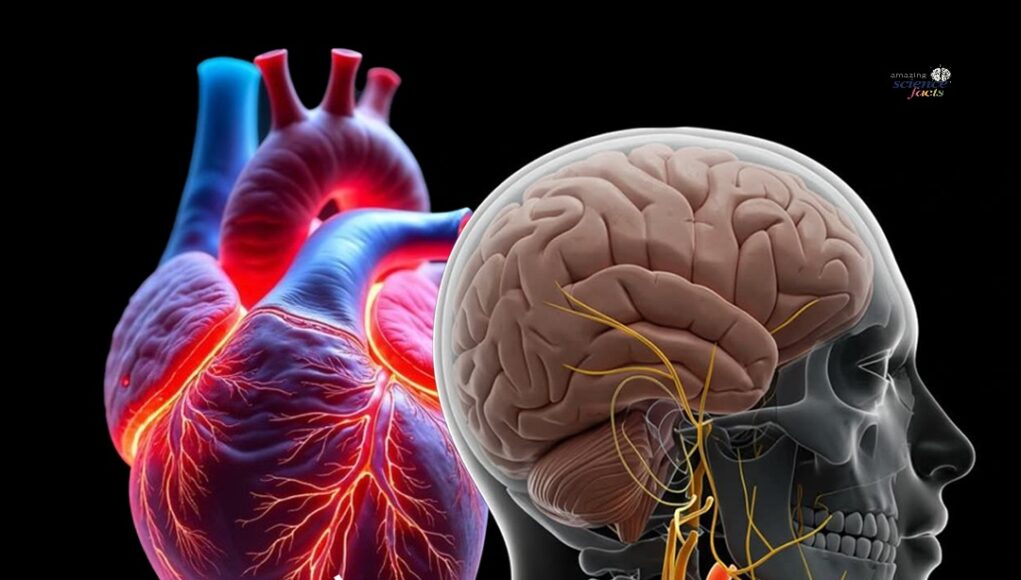

Tun Dr. Mahathir mengalami kecederaan pada pinggul kanannya setelah terjatuh di...

Bekas Perdana Menteri, Tun Dr. Mahathir Mohamad, telah disahkan mengalami keretakan pada pinggul sebelah kanan selepas terjatuh di rumahnya pada awal pagi ini.